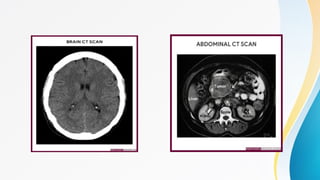

Plain Computed Tomography

Types Plain X-ray Plain ComputedTomography Plain Magnetic Resonance Imaging Plain Ultrasound